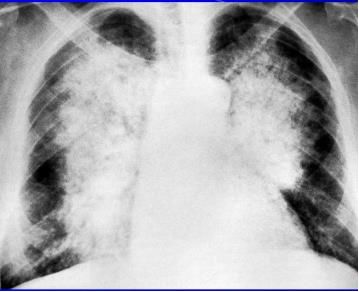

再来一个更直白的蝶翼征,几乎可以翩翩起舞了。